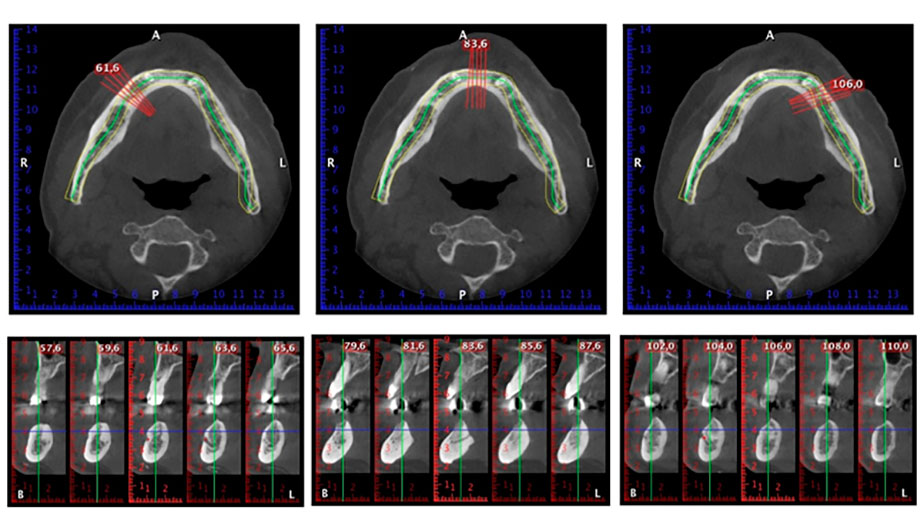

Zur Planung und Risikominimierung wurde eine dreidimensionale Volumentomografie (DVT, Planmeca) erstellt. Dieses zeigte, dass die Qualität und Quantität des Knochens für eine Operation und Sofortversorgung nach der Fast & Fixed-Methode ausreichend war. Nach Protokoll dieses Konzeptes wird in Regio 35, 32, 42 und 45 implantiert. Durch die bis zu 45-Grad-Schiefstellung der distalen Implantate wird das Durchtrittsprofil nach posterior verlegt und ein größeres Stützpolygon erreicht (Abb. 3).

Dies entspricht der nächsten Position der Voreinstellung am Implantmed. Zu erkennen ist die etwa 45-Grad-Schräghaltung des W&H Winkelstückes nach mesiokaudal in Regio 45, um den Nervus mentalis zu schonen. Das Foramen mentale gilt als anatomische Orientierung für alle Bohrungen in diesem Bereich. Die anschließenden Bohrungen werden mit einer reduzierten Umdrehungszahl von 300/min durchgeführt (Abb. 10 und 11).